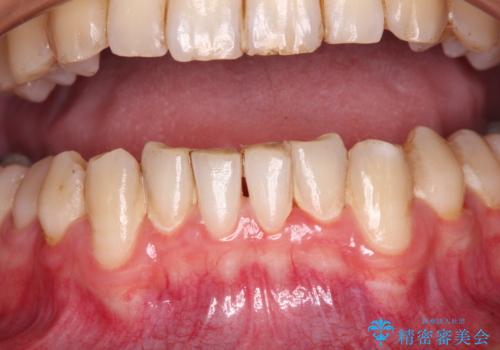

- 下顎犬歯の歯肉退縮を気にして来院された患者様です。

歯磨きの際にしみるとのことで、歯肉移植による根面被覆を行うこととしました。